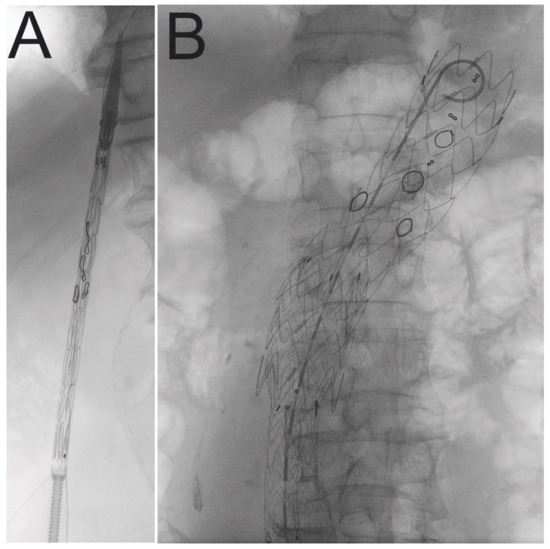

Figure 2.

Fluoroscopy view of modified stent graft including radiopaque fenestrations markers. Stent graft before (A) and after (B) deployment.

Both common femoral arteries were exposed or treated percutaneously with the Proglide device (Abbott, Chicago, IL, USA), depending on the vascular calcification state. This approach was used for PMEG advancement under Ziehm imaging guidance (Siemens, Munich, Germany) (Figure 2). In all cases PMEG was proximally deployed in zone 5 (above the celiac trunk). A snared-out preloaded soft guidewire was utilized to cannulate the SMA through the axillary artery. The left renal artery (LRA), the right renal artery (RRA), and SMA were targeted with balloon-expandable stents, while CT was left unstented. The bridging stents were from various companies: LifeStream (BD, Franklin Lakes, NJ, USA), Advanta V12 (Getinge, Goteborg, Sweden), BeGraft (Bentley InnoMed GmbH, Hechingen, Germany). A 10 mm × 20 mm angioplasty balloon was used to flare the stents. The distal stent graft component, which includes Endurant IIs (Medtronic, Dublin, Ireland), AFX 2 (Endologix, Irvine, CA, USA), Valiant Captiva extension (Medtronic, Dublin, Ireland), and Excluder (Gore, Newark, NJ, USA), was employed whenever necessary. For asymptomatic patients who had an aortoiliac stent graft implanted, the complete exclusion of the aneurysm from the circulation was split into two stages. The contralateral limb was implanted two to four weeks following the first stage. The staged procedure was designed to reduce the risk of paraplegia by temporary aneurysm sac perfusion [15]. Additionally, to reduce the risk of paraplegia, a hemoglobin level greater than 7 mmol/L and the mean arterial pressure greater than 90 mmHg were maintained. Drainage of cerebrospinal fluid was not routinely used. After the procedure, all patients were advised dual antiplatelet therapy. All patients were compliant with medical treatment.